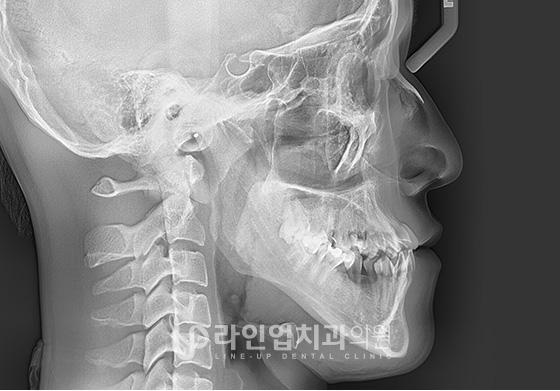

ЭТАПЫ ОПЕРАЦИИ

01

Резекция челюсти с задней стороны моляров до височно-нижнечелюстного сустава

02

В зависимости от плана операции челюсть перемещается в нужное положение

03

Фиксируется специальными пластинами

ФОТО ДО И ПОСЛЕ

Before

After